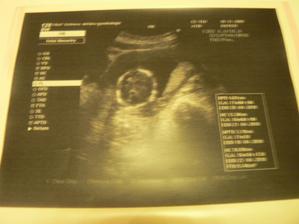

30.11.09 jsme byli na velkém genetickém UTZ a na srdíčku vše je v pořádku a vypadá to že jsem holčička 🙂 a vážím 350 g